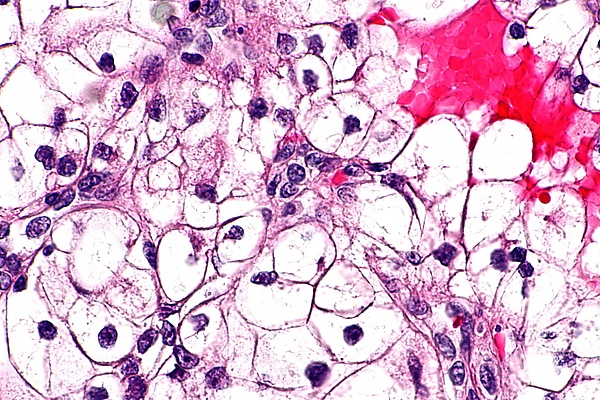

Гистологические особенности светлоклеточного рака почки

Клетки светлоклеточного рака почки обычно имеют светлую, прозрачную цитоплазму, хорошо различимую клеточную мембрану, и содержат шарообразное, более или менее обычно выглядящее, ядро[2].

Консенсусом экспертов ВОЗ предложена следующая градация степени злокачественности светлоклеточного рака почки по микроскопически наблюдаемой гистологической картине[2]:

• 1-я степень: Клетки опухоли имеют базофильное и, в целом, не выглядящее сколь-нибудь подозрительным, ядрышко, которое с трудом различимо при увеличении в 400 раз;

• 2-я степень: Клетки опухоли имеют очерченное, хорошо различимое при увеличении в 400 раз ядрышко с эозинофильной, а не с базофильной окраской;

• 3-я степень: Клетки опухоли имеют очерченное и более крупное, чем в первых двух случаях, ядрышко, которое хорошо различимо уже при увеличении не в 400, а всего в 100 раз;

• 4-я степень: Клетки опухоли проявляют высокую или очень высокую (исключительную) степень плеоморфизма (то есть морфологически мало похожи одна на другую, имеют необычно большие различия строения и внешнего вида), выглядят низкодифференцированными, или же имеют рабдоидную либо саркоидную морфологию.